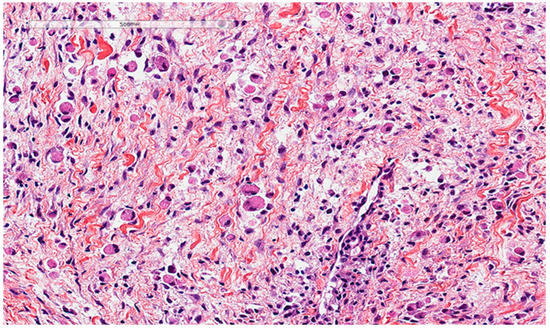

6. Differential Diagnoses